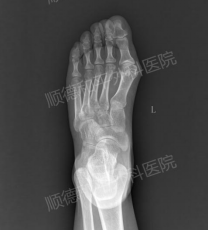

入院当天摄,可见拇外翻在向第二趾叠合发展

入院后,经骨四区程忠勇主任及傅志均主治医师仔细查体和询问病情,及摄片检查后,张女士确诊为:左足第1趾中度外翻并收住院。

所幸摄片时发现关节面对合关系尚可,所及诸骨骨质结构完整,骨纹理连续,未见明确骨折或骨质破坏,各关节在位,关节间隙清晰。仅需行左足拇外翻微创截骨矫形内固定即可。